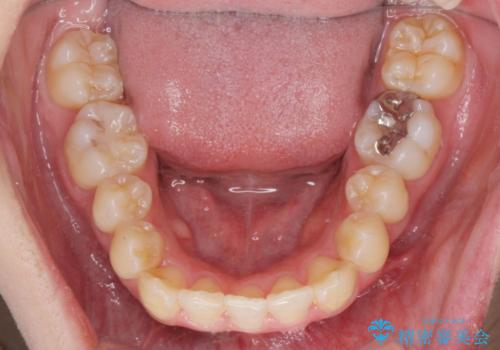

前歯のがたつきをマウスピース矯正できれいに!

- 1年8ヶ月

- 目立つ前歯のがたつきを改善したい、と矯正治療を希望され来院されました。

今回の治療ではシミュレーションでしっかりと検討した結果、下顎は前歯を1本抜去し仕上げる治療計画としました。